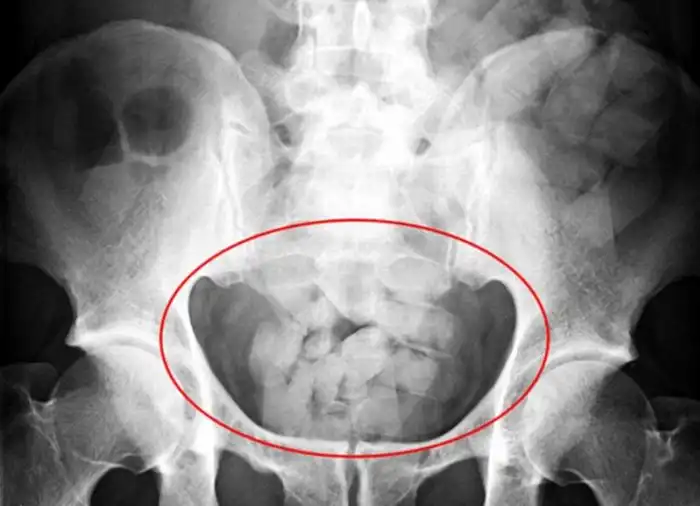

20 контейнеров с наркотиками в толстой кишке

100 пакетиков кокаина в желудке

Наркотики в толстой кишке